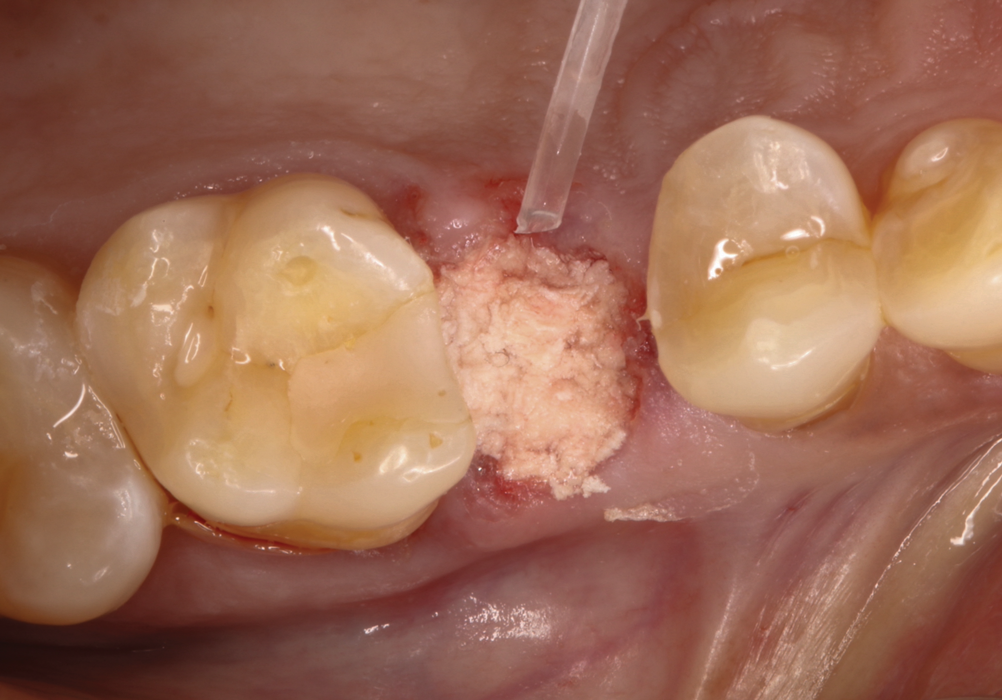

Fig 1. Hopeless maxillary second premolar.

Figure 1

The absorbable bone scaffold material (Figure 3) was quickly hydrated in a sterile saline solution and adapted into the extraction socket with cotton pliers. The material was placed to the level of the adjacent soft-tissue margin, and any excess was removed (Figure 4). Light pressure with a dampened gauze was applied for 1 minute, allowing blood clot formation around the bone scaffold. Fast-setting cyanoacrylate adhesive dressing was used to seal the coronal aspect of the absorbable bone scaffold (Figure 5).

In the case presented, a 56-year-old male patient had a coronal fracture on tooth No. 13, which was deemed hopeless (Figure 1). Treatment options were discussed with the patient, including endodontic therapy followed by surgical crown lengthening with forced tooth eruption to expose sound tooth structure for prosthetic tooth reconstruction. Due to the short length of the residual root, however, an unfavorable prognosis was assigned to this treatment option. The clinician determined, therefore, that replacement of the tooth with a dental implant would be the most conservative, viable, and predictable option for tooth replacement since significant tooth reduction of unrestored adjacent teeth would be necessary for three-unit fixed-bridge fabrication and the patient did not accept any removable replacement options.